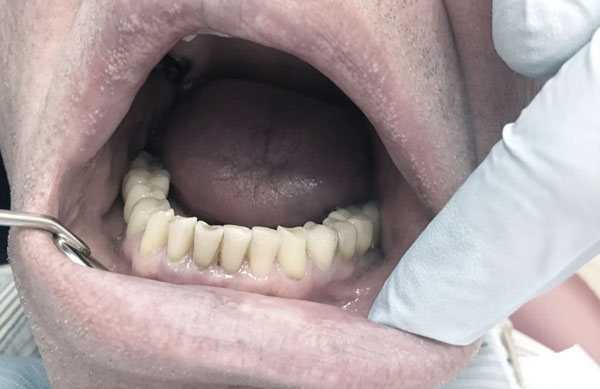

Рис.1 Этап экстракции зубов 31,41 с подвижностью 3-4 степени

Обязательной тактикой немедленной имплантации следует считать атравматичную экстракцию зубов во фронтальном отделе, которая производится с помощью тонких элеваторов. Осуществление люксации при данном оперативном подходе возможно только   с медиальной, дистальной и оральной стенок альвеолы во избежание перфорации вестибулярной стенки апикальной частью имплантата (Рис.1). Даже при остеоинтеграции имплантата при повреждении вестибулярной стенки эстетика будет нарушена. Поэтому после проведения немедленной имплантации 3D-томография снова является идентификатором показателей инклинации имплантата, глубины его погружения в губчатый слой, выявления дефектов костной структуры (Рис.2,3,4,5,6).